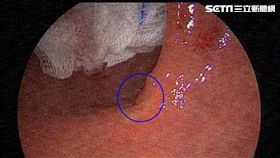

生活規律53歲教師 血便月餘竟罹癌

台中53歲王老師最近發現排便習慣改變,且肛門出血情形...

2019/01/15 10:40